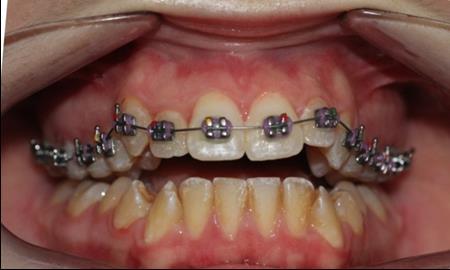

The patient, a 21-year old woman , had a convex profile , class I dental malocclusion ,anterior open bite of 4 mm . She was a mouth breather and presented tongue thrust. Her chief complain was the anterior open bite .(Figure 1)

Figure 1.Pretreatment intraoral photography

Pretreatment intraoral photography